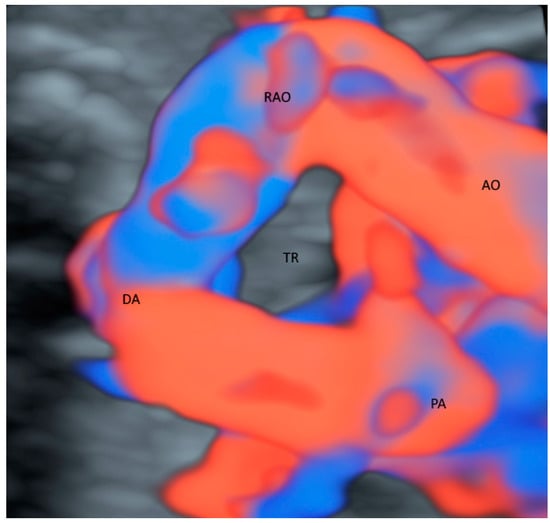

2.1. Outflow Tracts

| Heart/chest | High flow (CDFI) Small/low flow (HDFI) | GBM | Abnormal outflow tracts Course of trachea in right aortic arch Pulmonary vessels in lung dysplasia Liver vessels in diaphragmatic hernia Esophageal pouch in esophageal atresia |